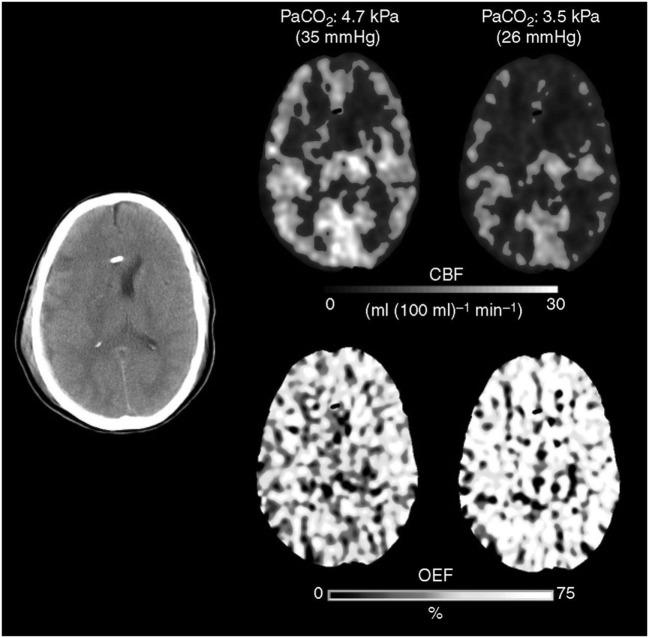

During traumatic brain injury, intracranial hypertension (ICH) can become a life-threatening condition if it is not managed quickly and adequately. Physicians use therapeutic hyperventilation to reduce elevated intracranial pressure (ICP) by manipulating autoregulatory functions connected to cerebrovascular CO reactivity. Inducing hypocapnia hyperventilation reduces the partial pressure of arterial carbon dioxide (PaCO), which incites vasoconstriction in the cerebral resistance arterioles. This constriction decrease cerebral blood flow, which reduces cerebral blood volume and, ultimately, decreases the patient's ICP. The effects of therapeutic hyperventilation (HV) are transient, but the risks accompanying these changes in cerebral and systemic physiology must be carefully considered before the treatment can be deemed advisable. The most prominent criticism of this approach is the cited possibility of developing cerebral ischemia and tissue hypoxia. While it is true that certain measures, such as cerebral oxygenation monitoring, are needed to mitigate these dangerous conditions, using available evidence of potential poor outcomes associated with HV as justification to dismiss the implementation of therapeutic HV is debatable and remains a controversial subject among physicians. This review highlights various issues surrounding the use of HV as a means of controlling posttraumatic ICH, including indications for treatment, potential risks, and benefits, and a discussion of what techniques can be implemented to avoid adverse complications.

在创伤性脑损伤期间,如果颅内高压(ICH)得不到迅速且充分的处理,可能会成为危及生命的状况。医生采用治疗性过度通气,通过操纵与脑血管二氧化碳反应性相关的自动调节功能来降低升高的颅内压(ICP)。诱导低碳酸血症(过度通气)会降低动脉血二氧化碳分压(PaCO₂),这会引发脑阻力小动脉的血管收缩。这种收缩会减少脑血流量,进而减少脑血容量,并最终降低患者的颅内压。治疗性过度通气(HV)的效果是短暂的,但在认为该治疗方法可取之前,必须仔细考虑伴随这些脑和全身生理变化的风险。对这种方法最突出的批评是提到的发生脑缺血和组织缺氧的可能性。虽然确实需要采取某些措施,如脑氧合监测,来减轻这些危险状况,但以与HV相关的潜在不良后果的现有证据为理由摒弃治疗性HV的实施是有争议的,并且在医生中仍然是一个有争议的话题。这篇综述强调了围绕使用HV作为控制创伤后ICH的一种手段的各种问题,包括治疗指征、潜在风险和益处,以及对可以实施哪些技术来避免不良并发症的讨论。